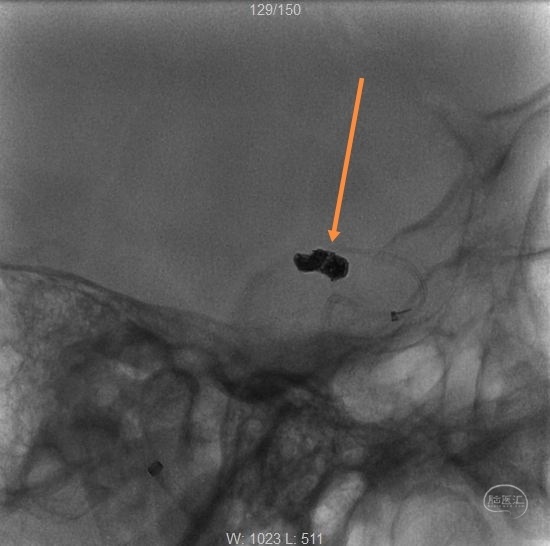

两根微导管到位(箭头示微导管2),先经过微导管1植入一枚,三维Target3-4弹簧圈,不解脱。

再经过微导管2植入一枚,三维Target2-6弹簧圈。

再经过微导管2,植入一枚二维target2-4弹簧圈。